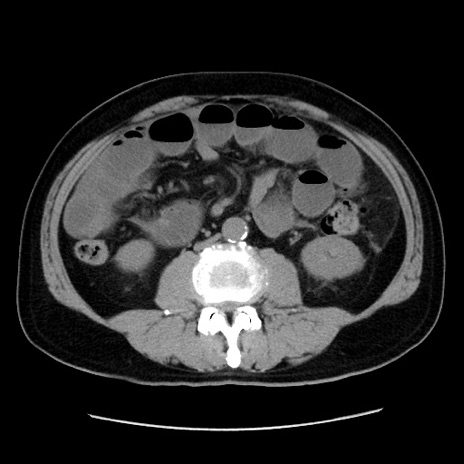

冠状断像

症例16(横断像)

【症例】 70歳代男性

【主訴】 腹痛、嘔吐

【現病歴】 約1ヶ月前より間欠的に腹痛と嘔吐あり、当院消化器内科を受診したところCTで多発する肝臓のLDAを指摘され、精査中であった。以降は消化器症状は安定していたが、2日前より嘔気と腹痛があり、同日より排便・排ガスが消失した。改善認めず、 本日、救急外来を受診した。

【既往歴】 大腸ポリープ切除後。

【身体所見】意識清明・会話良好、BT 36.3℃、BP 127/80mmHg、 P 80bpm、腹部:膨満あり、平坦・軟、上腹部正中および下腹部正中に圧痛あり、反跳痛なし、筋性防御なし。

【データ】WBC 7200、CRP 0.77